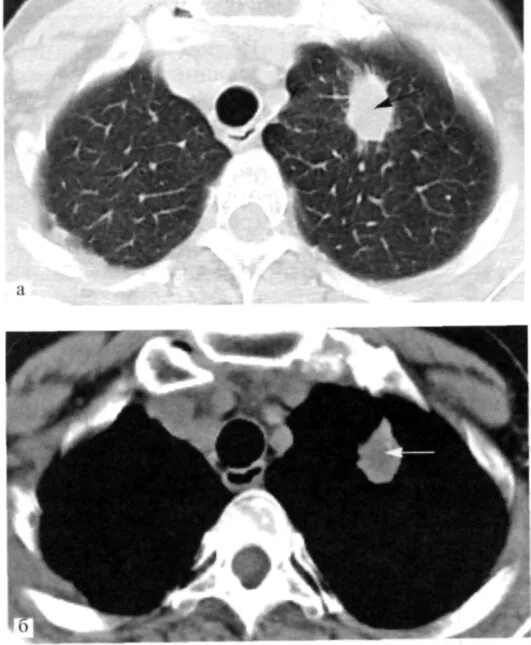

Единичные солидные узелки в легких